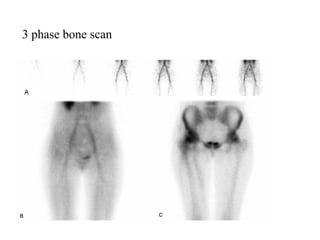

3 phase bone scan

 Three phases which represent the distribution of

the tracer over the course of time

 Phase 1 – Flow phase or radionuclide angiogram -

tracer is intravascular – images are obtained every 2-

3 seconds for 30 seconds

 Phase 2 – Blood pool phase – the tracer is located in

the extravascular space – the body is imaged 5

minutes after injection

 Phase 3 – Bone scan phase – 2-4 hours after

injection – represents clearance of the tracer from the

vessels and soft tissues and concentration into the

skeleton